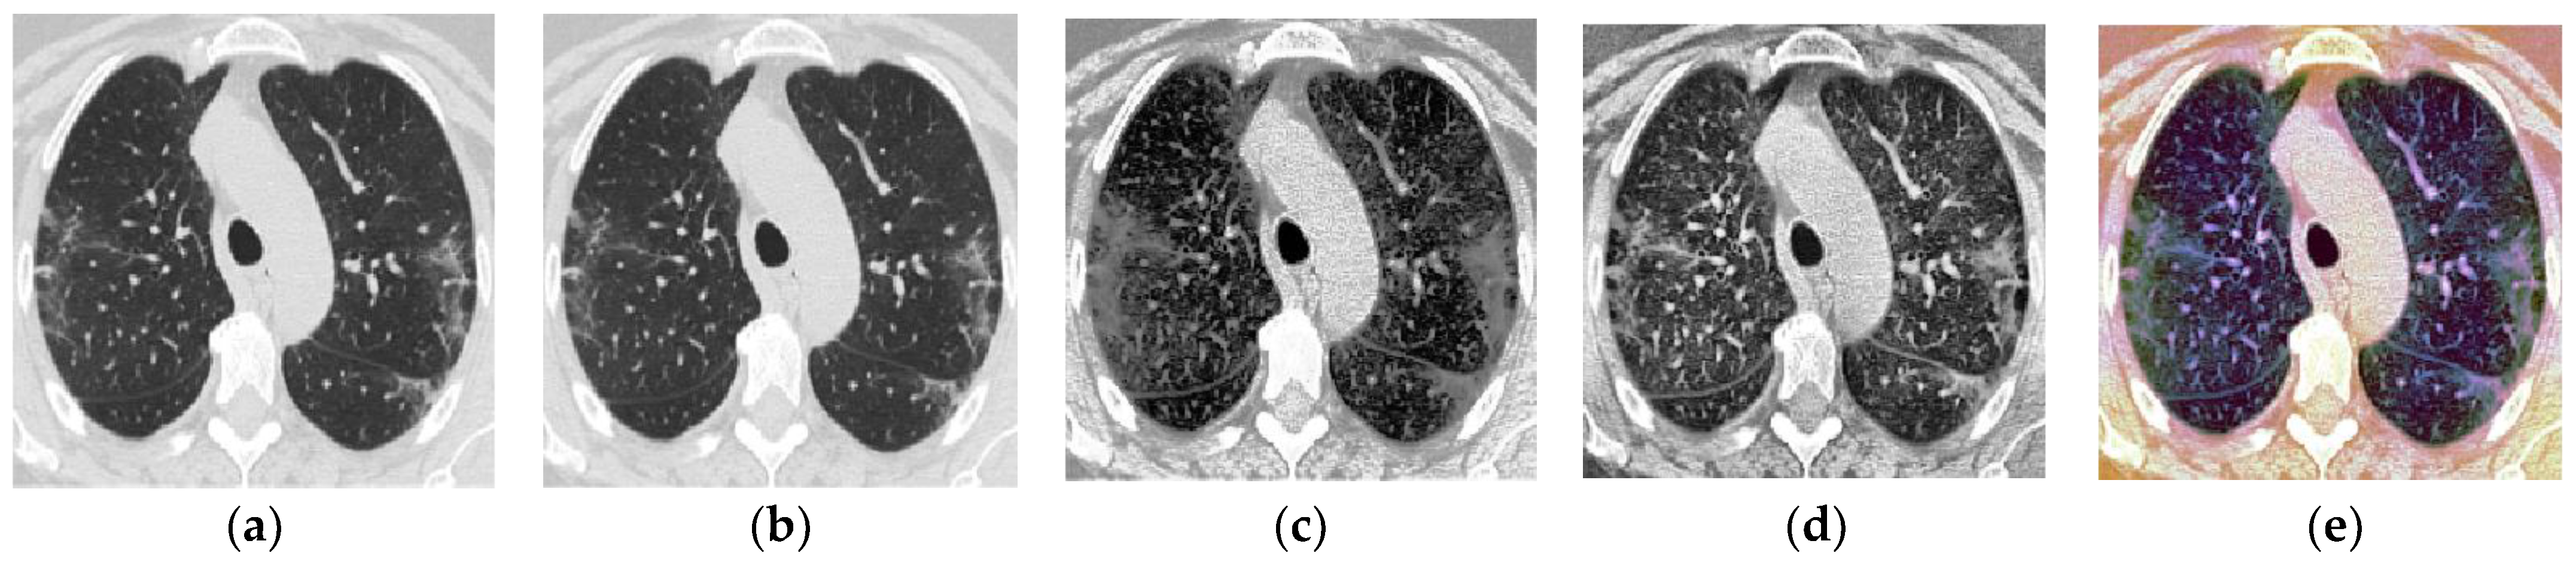

For the GRAY3_CLAHE image, another enhancement method called Contrast Limited Adaptive Histogram Equalization (CLAHE) is used. This technique is applied directly to the one-channel grayscale image using the Tensorflow function called ‘tfa.clahe()’. Then, another three-channel image is formed using the output of this step. Specifically, we copy the one-channel image (the grayscale image enhanced using CLAHE) to create a three-channel CLAHE image. Last but not least, another image representation called GRAY+GRAY_HE+GRAY_CLAHE was also proposed in this study. The formation of this image representation starts by creating three one-channel grayscale images in parallel. Then, we applied HE to one of the grayscaled images and CLAHE to another image. The last grayscale image remained unenhanced. After that, these three images are stacked together to form a three-channel image consisting of a grayscale image, an equalized image, and a CLAHE image. Table 2 is prepared to facilitate the presentation of findings throughout this paper, briefly describing the five image representations. A sample CT image for each representation is also presented in Figure 2. Figure 2a shows a sample of one original CT image that belongs to the COVID-19 class after rescaling.

As shown in Figure 2, although it appears as a grey image, it has RGB color space (three-channel image) without any bias toward red, green, or blue hue. In other words, all the original CT images in the SARS-CoV-2 dataset are technically RGB images, but they still appear grey as the three RGB channels are identical.

Figure 2. Sample image after data pre-processing for each image representation: (a) RGB, (b) GRAY3, (c) GRAY3_HE, (d) GRAY3_CLAHE, (e) GRAY+GRAY_HE+GRAY_CLAHE.